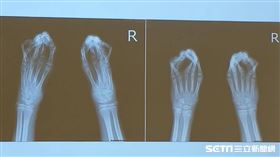

他出生「鴨掌手」!15年來無法抓握

一名出生在緬甸果敢地區今年15歲的小男孩張子墨,一出...

2019/12/23 11:55